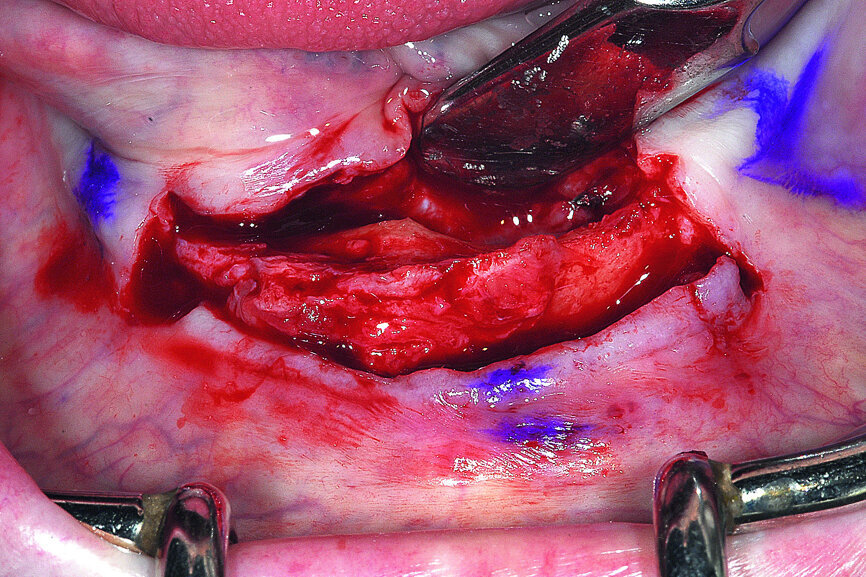

Based on the CBCT data and interactive treatment planning simulations, it was elected to complete the surgical placement of four implants in the anterior symphysis in a ‘diagnostic-freehand’ manner. The anatomical landmarks were clear and allowed the accuracy of implant positioning. The knife-edged ridge required a full flap surgical approach (Fig. 13).

Fig. 13: A full thickness mucoperiosteal flap exposed the knifeedged ridge of the mandibular symphysis.

Once the offending element was removed, the plan was to reduce the knife-edged ridge to gain appropriate width for implant placement. The reduction was accomplished in a free-hand method based upon the position and location of the mental foramen on either side of the symphysis. Based upon a thorough review of the CBCT scan data the expected hollow area of bone in the anterior symphysis was exposed (Fig. 15).